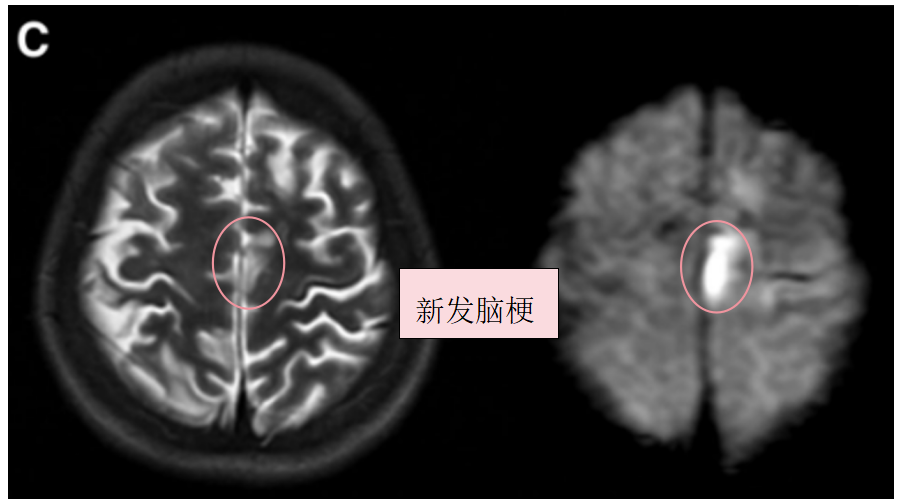

约1个月后,患者因“构音障碍及右腿无力”再次入院。复查影像提示左额叶新发脑梗死。

术前T2、DWI序列显示左额叶新发展的脑梗死。